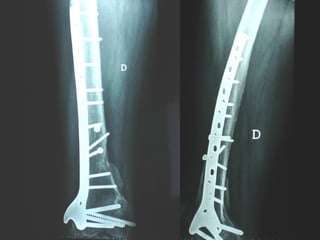

Dal Gennaio 2000 al Febbraio 2006 abbiamo trattato 167 fratture chiuse  con placca percutanea  in 164 pazienti :  27 lesioni diafisarie di gamba, 12 piloni tibiali ,  11 fratture prossimali di tibia, 36 fratture sovracondiloidee di femore, 17 fratture diafisarie di femore, 43 fratture metaepifisarie prossimali di omero, 21 diafisarie d’omero.  156 guarigioni 8 fallimenti

Dal Giugno 2002 al Dicembre 2004 abbiamo trattato 5 fratture esposte: 3 di tibia e 2 di ulna 5 guarigioni

I buoni risultati ottenuti dipendono da 5 punti fondamentali:   una accurata riduzione percutanea della frattura  precise vie di accesso  l’utilizzo della placca che consenta il più lungo braccio di leva possibile il pretensionamento della placca  una sintesi con un ridotto numero di viti

Placche lunghe e pretensionate Sintesi con un ridotto numero di viti

2 Insuccessi

Fratture  esposte